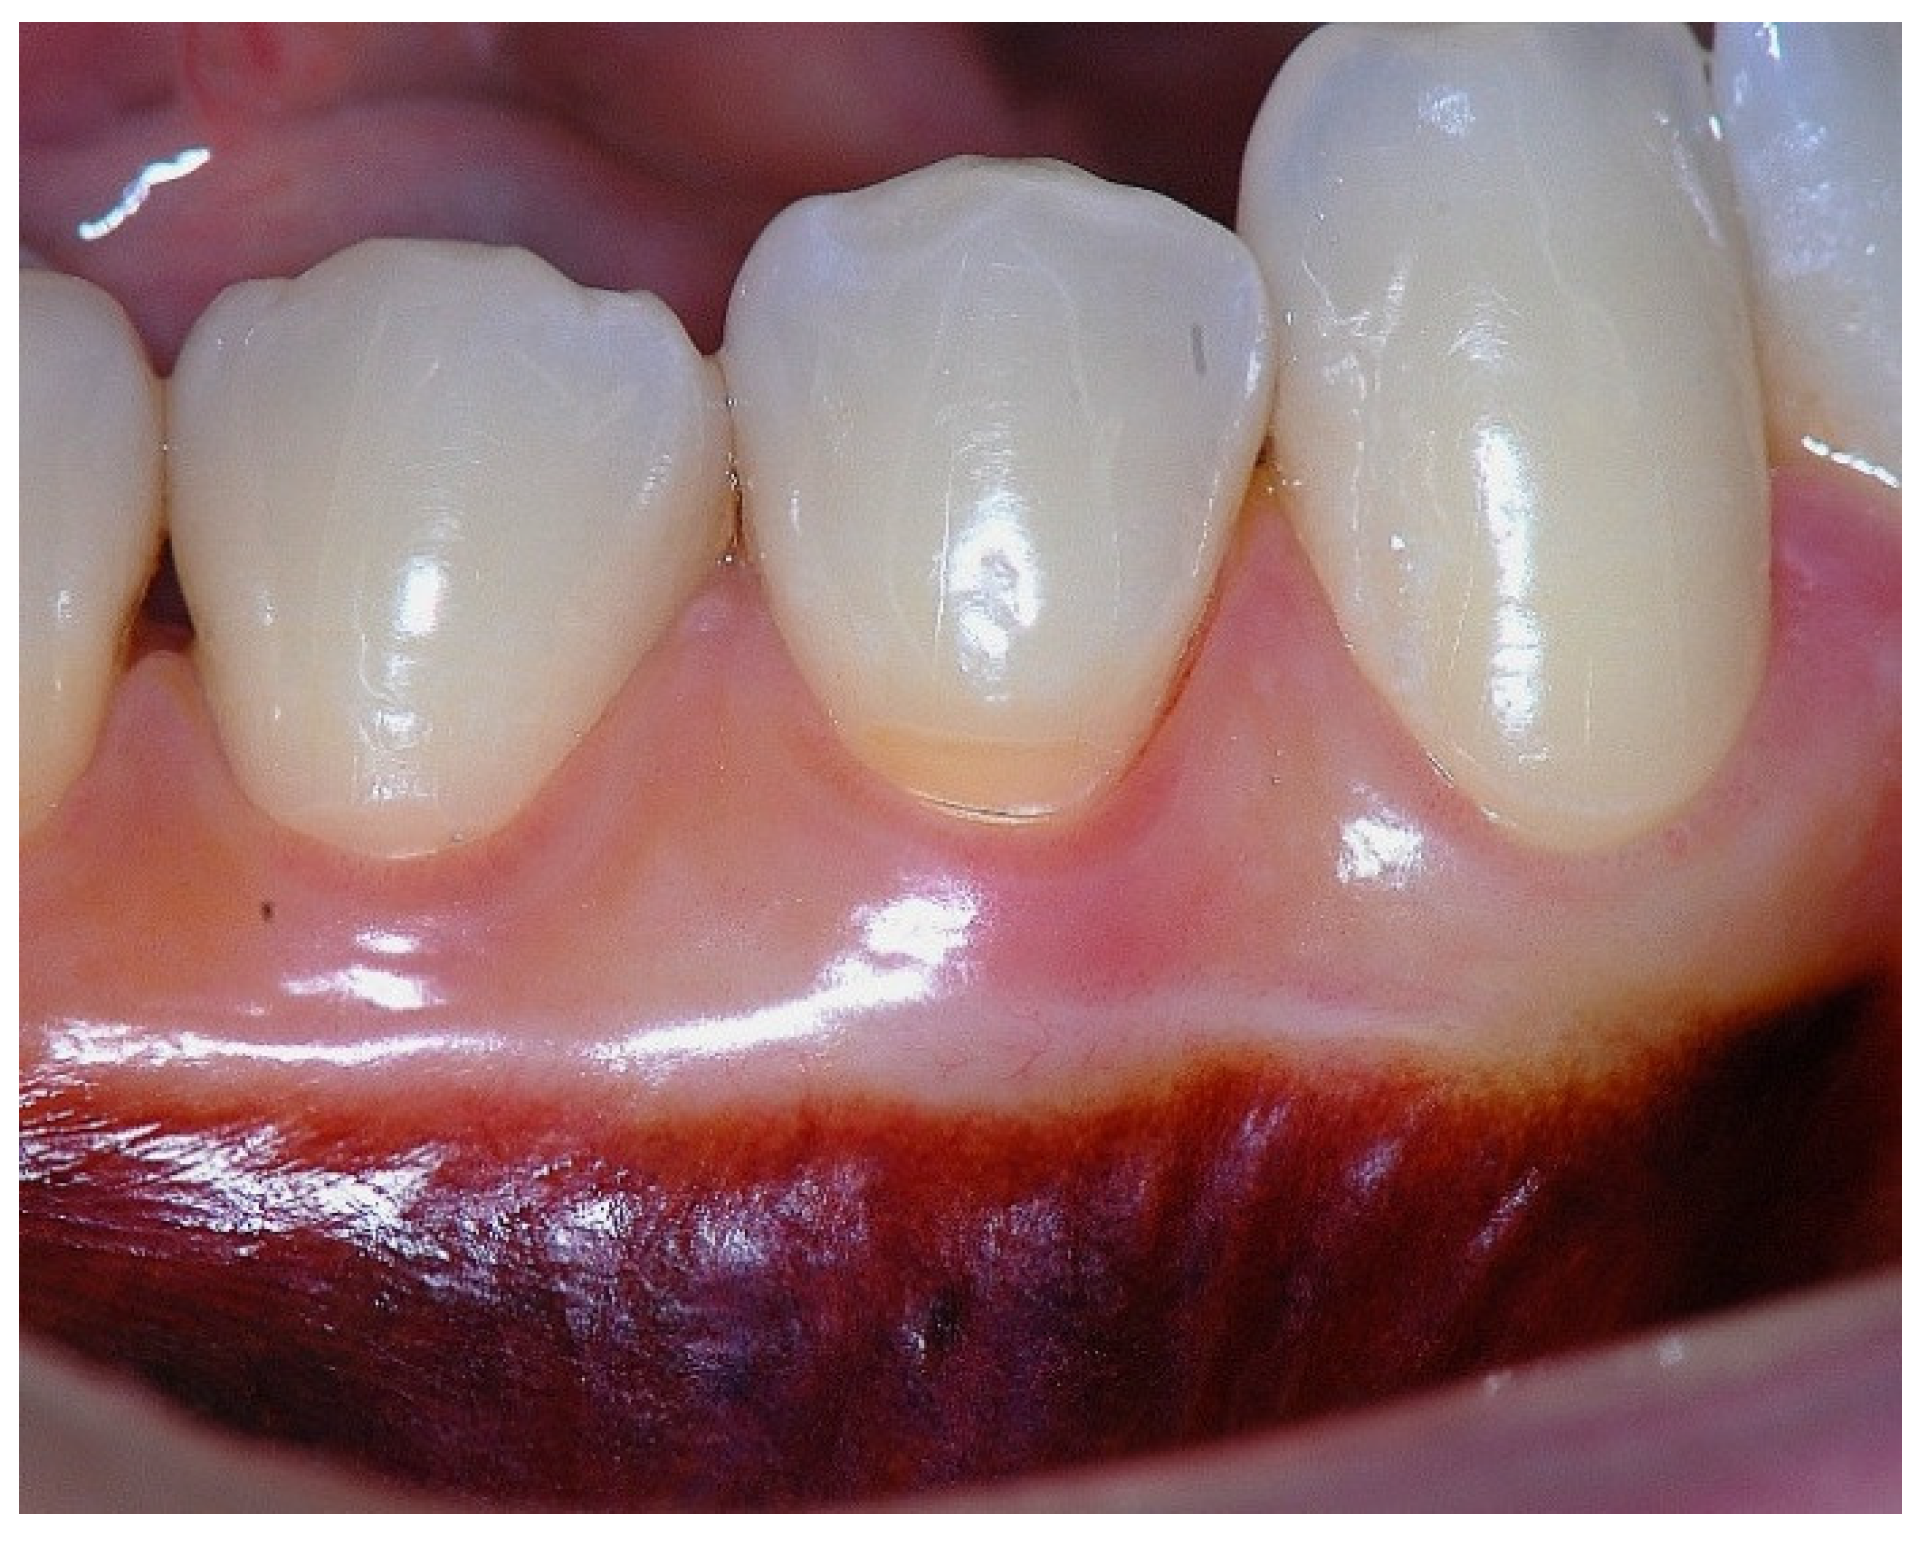

Figure 5. Apical displacement of the gingival margin observed during deep lip retraction.

In a clinical scenario with 2 mm of keratinized tissue (KT) and a sulcus depth of 1 mm, a stable, firm, and resistant connective attachment is not present [1]. This occurs because most of the connective tissue fibers inserting onto the root surface are associated with non-keratinized, mobile mucosal tissues (Figure 1), which are elastic in nature and therefore unable to stabilize the gingival margin (Figure 4 and Figure 5). Conversely, when these fibers are embedded within keratinized tissue, they are firmly attached to the tooth and bone and are comparatively immobile, thereby contributing to gingival margin stability (Figure 2, Figure 3, and Figure 6).